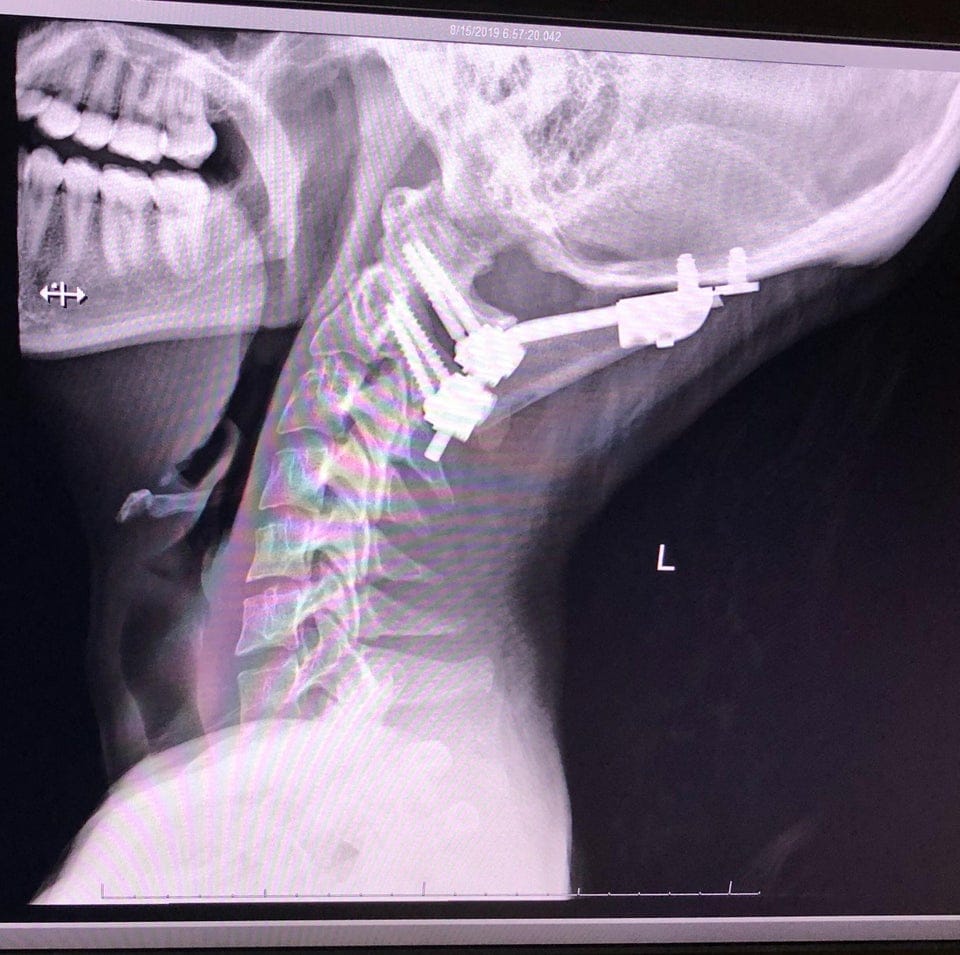

Медичний пристрій для лікування перелому шиї